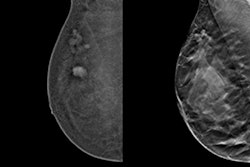

Kheiron, founded in 2016 and headquartered in London, develops deep-learning AI software to identify malignancies in mammograms. Its CE-marked software Mia was deployed in Europe in the U.K.’s first prospective evaluation of AI technology for breast cancer screening, DeepHealth said.